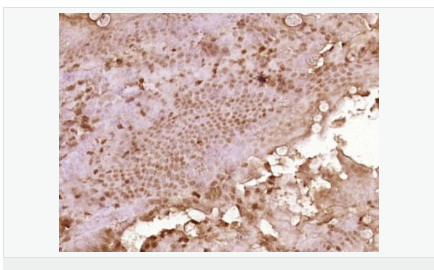

產(chǎn)品應(yīng)用WB=1:500-2000 ELISA=1:5000-10000 IHC-P=1:100-500 IHC-F=1:100-500 ICC=1:100-500 IF=1:100-500 (石蠟切片需做抗原修復(fù))

細(xì)胞定位細(xì)胞漿

產(chǎn)品介紹C3orf32 (chromosome 3 open reading frame 32), also known as fls485, is a 353 amino acid protein encoded by a gene that maps to human chromosome 3p26.1. Chromosome 3 is made up of approximately 214 million bases encoding over 1,100 genes. Notably, there is a chemokine receptor gene cluster and a variety of human cancer related loci on chromosome 3. Particular regions of the chromosome 3 short arm are deleted in many types of cancer cells. Key tumor suppressing genes on chromosome 3 encode apoptosis mediator RASSF1, cell migration regulator HYAL1 and angiogenesis suppressor SEMA3B. Marfan Syndrome, porphyria, von Hippel-Lindau syndrome, osteogenesis imperfecta and Charcot-Marie-Tooth disease are a few of the numerous genetic diseases associated with chromosome 3.

Expressed in enterocytes of small and large intestinal mucosa (at protein level). Expressed in enterocytes, chromaffine and interstitial cells.